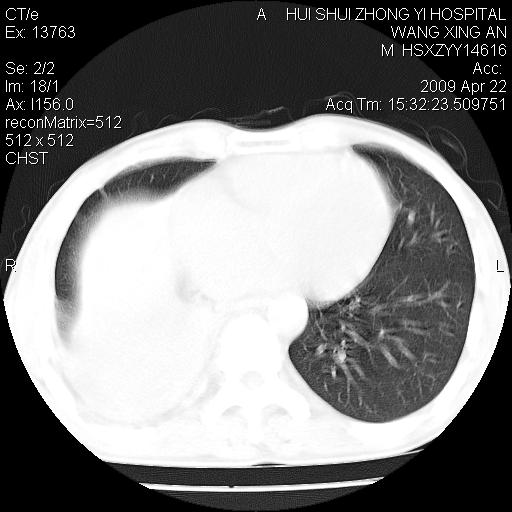

标题: CT19534:患者男、46岁咳嗽、胸痛半月。 [打印本页]

标题: CT19534:患者男、46岁咳嗽、胸痛半月。

考虑---右肺中心型肺癌继发下叶不张,少量胸水。

支持右侧中央型肺ca并右下肺不张、右侧胸腔少量积液。

1、右下肺中央型肺癌并右肺转移,右肺下叶不张。(肿块围绕右肺下叶支气管生长,致管腔闭塞右肺下叶不张;右肺有结节影)。

2、右侧胸腔积液。

3、右中上肺陈旧性肺结核(右肺见纤维化病灶及点状钙化)。